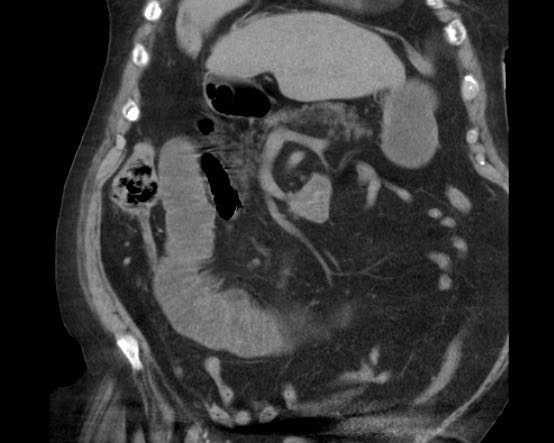

CT trong viêm túi mật cấp

CT có thể rất hữu ích trong các trường hợp siêu âm không cho kết quả chẩn đoán.

Đây là hình ảnh của một bệnh nhân béo phì với đau hạ sườn phải cấp tính trong 6 giờ. CRP 2.

Siêu âm cho thấy túi mật lớn có bùn mật, không quan sát thấy sỏi.

Việc ấn vào túi mật không đáng tin cậy do vị trí cao dưới cung sườn phải.

Không có bất thường siêu âm nào khác.

CT thực hiện cùng ngày cho thấy túi mật lớn với chỉ những thay đổi quanh túi mật kín đáo và không có nguyên nhân nào khác giải thích cho các triệu chứng.

Ngày hôm sau CRP là 105 và CT không tiêm thuốc cản quang lặp lại cho thấy quầng mờ xung quanh túi mật.

Phẫu thuật tiếp theo xác nhận viêm túi mật cấp giai đoạn sớm do sỏi nhỏ trong ống túi mật.